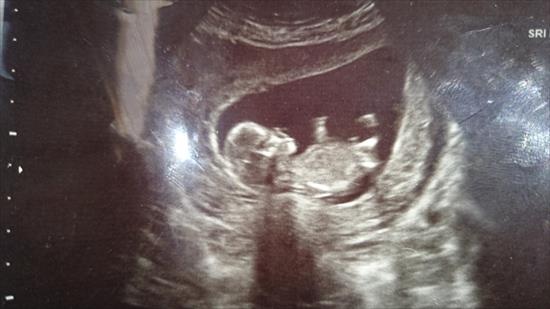

Here is another 12 + 3 pic. Not sure if shows anything?

Slight girl lean - not sure if the leg is hiding some nub :)

Maybe girl

I am leaning girl.